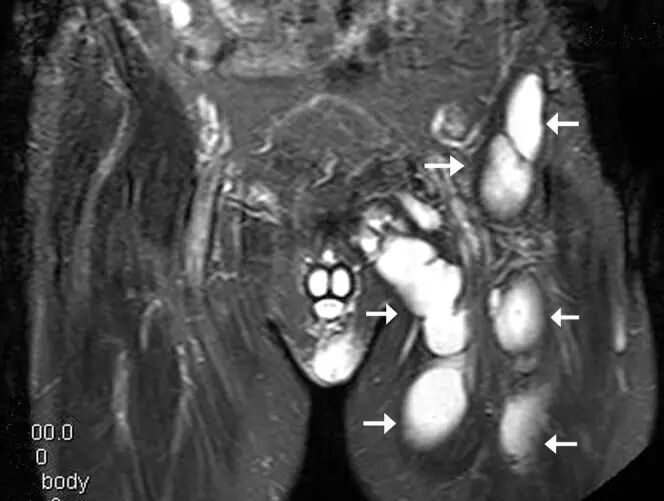

图7.一位52岁的男性,糖尿病控制不良,在大腿近端,臀部和肌肉梗死时突然出现严重疼痛。a)冠状脂肪抑制T2加权磁共振图像显示在涉及闭孔外肌,耻骨肌和短收肌和长肌的前内侧大腿的广泛的肌内水肿(箭头)。 在闭孔外肌和耻骨肌之间注意到少量流体(箭头)。(b)轴向T2加权的MR图像显示在延伸通过臀大肌的内收物中的弥漫性水肿。 在内转子中看到高信号积液(箭头)。

![]()